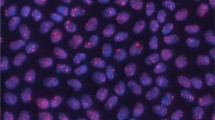

γH2AX foci assay

Cells (lymphocytes and LECs) were placed in the incubator (37 °C, 5% CO2); 1, 4 and 24 h after irradiation, they were fixed in 2% PFA for 15 min. Wells with fixed LECs were rinsed with phosphate-buffered saline (PBS), incubated three times for 5 min with PBS containing 0.15% Triton-X100 and blocked three times for 10 min with blocking solution (PBS containing 1% BSA and 0.15% glycine). LECs were incubated with the primary antibody Phospho-Histone H2A.X (Ser139) (20E3) (NEB, CellSignaling, Frankfurt am Main, Germany) 1:400 in blocking solution overnight at 4 °C. LECs were washed with PBS three times and incubated with an anti-Rabbit IgG (H + L) secondary antibody, Alexa Fluor 488 (Thermo Fisher Scientific) 1:250 in blocking solution for 1 h at room temperature. Afterwards, the cells were washed in PBS three times and incubated with DAPI (D9564, Sigma Aldrich Chemie, Taufkirchen, Germany; dilution 1:10,000) for 15 min, washed with PBS twice, air dried in the dark and covered with mounting medium (Ibidi, Martinsried, Germany). For foci analysis, an automated scanning and analysis system was used (Axioplan 2; Carl Zeiss, Jena, Germany; Metafer4, Metasystems, Altlußheim; Germany).

DNA repair in primary lens epithelial cells and in spleen lymphocytes. a Primary lens epithelial cells and spleen lymphocytes from wild types and heterozygous Ercc2 mutants (het) were irradiated by 0.5 Gy, and 1 h later DNA damage was visualized by antibodies against γH2AX (green, Alexa Fluor 488; red, Alexa Fluor 555); cell nuclei were counterstained by DAPI (blue). DNA damage after irradiation was measured by γH2AX response after 1 (b), 4 (c) and 24 (d) h. A significant dose-dependent increase of DNA damage can be observed, which is not detected after 24 h. There is no difference between sex and genotype